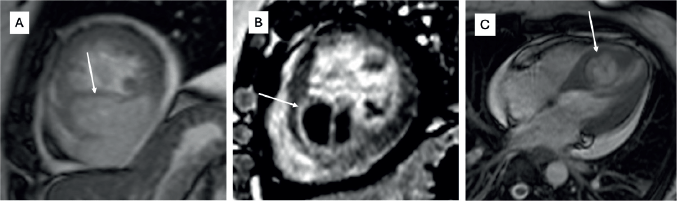

Figure 1. Cardiac MRI of a patient with synovial sarcoma of interventricular septum – (a): Bright blood (SSFP sequence) in short-axis view showing the heterogeneously hyperintense mass lesion (arrow) involving the septum and extending into the inferior wall of the left ventricle; (b): Late gadolinium enhancement (LGE) sequence in short axis view showing heterogenous peripheral enhancement with central non-enhancing component; (c): Bright blood (SSFP sequence) in four chamber view showing the mass (arrow) with cystic appearance within it.

Primary cardiac sarcomas are rare and the prognosis is not encouraging. It is a disease often seen in middle-aged patients with a slight male predominance. In our study, the median age was 33 years (range 17–53 years) and had male predominance. The most common site of primary lesion in a cardiac sarcoma is right atrium and most often angiosarcoma is found to be the cause, which is reflected in the present study as well. Siontis et al [7] stated that 46% patients present with metastatic disease upfront. In the present case series, 33.3% had a metastatic disease at presentation. Although literature shows that some cardiac sarcomas can initially be misdiagnosed as a benign cardiac pathology, the exact percentage is not clear. In our study, 50% of patients were misdiagnosed at presentation, which led to a median delay of 1.75 months losing precious time in treatment initiation and were found to have extensive disease/metastatic disease at the time of diagnosis. This highlights that cardiac sarcomas can have certain atypical features on imaging modalities like echocardiography or cardiac MRI and hence, definitive diagnosis should always be based on histopathology. In a developing country like ours, tubercular involvement of right heart is not very uncommon and hence right-sided angiosarcomas may be misdiagnosed as the same. Also, cystic appearance of sarcoma can sometimes defy the usual diagnostic features, like in one of our cases, where it masqueraded as a hydatid cyst (Figure 1) [20].